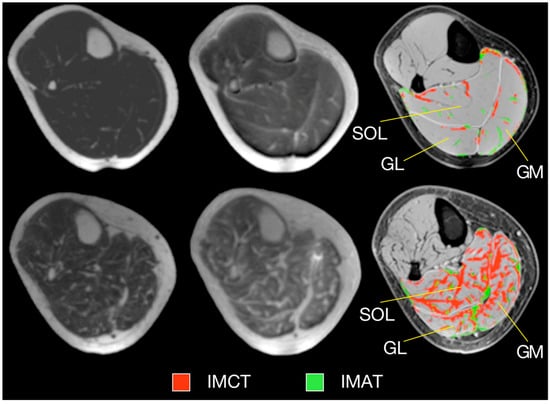

- Ugarte, V.; Sinha, U.; Malis, V.; Csapo, R.; Sinha, S. 3D multimodal spatial fuzzy segmentation of intramuscular connective and adipose tissue from ultrashort TE MR images of calf muscle. Magn. Reson. Med. 2017, 77, 870–883. [Google Scholar] [CrossRef] [PubMed][Green Version]